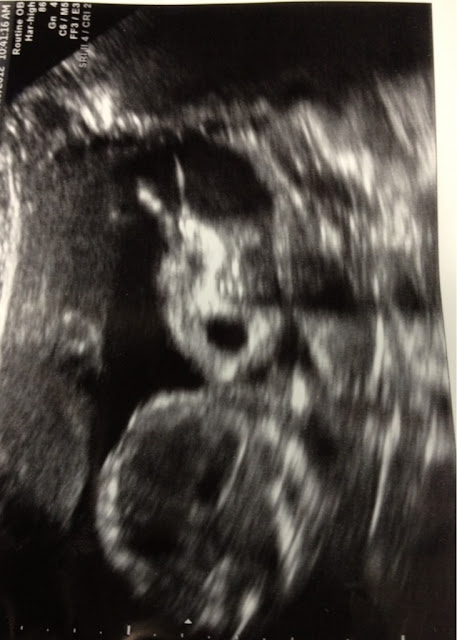

| Here she is yawning. She is also giving herself bunny ears:) |

| Sweet little profile |